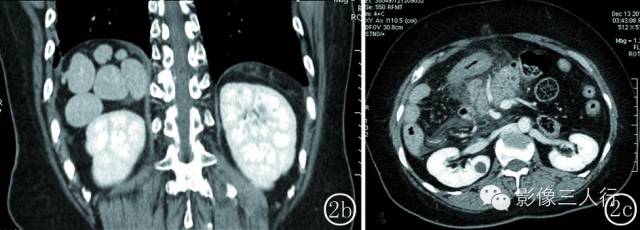

图 2 女性 , 52 岁 。 图 2a 水平肝 ,胃 、脾反位 ,均位于右季肋区 ,脾呈多个大小不等的结节 ,肝段下腔静脉缺如 ,奇静脉及半奇静脉异常增粗 。 图 2b冠脉位重建图像 :右侧季肋区可见 6 个大小不等的小脾脏 。 图 2c 胰腺反位 ,胰腺体尾部发育短小 ,胰腺周围可见渗出 ,双侧肾静脉回流入奇静脉